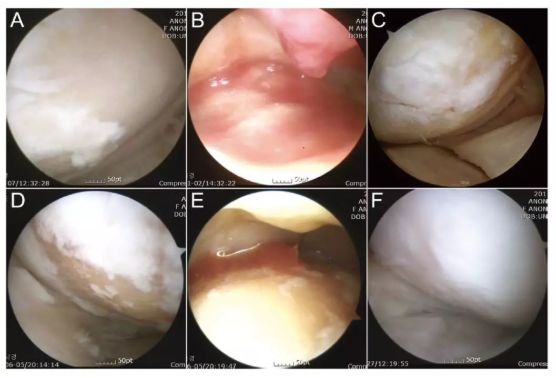

評估指標:IKDC 評分丨關節鏡檢查丨主訴

研究結果:ADSCs 治療可以顯著改善膝骨關節炎,BMI 越高效果越差。

注:上圖中 A-C 為 51 歲男性膝關節鏡,D-F 為 54 歲女性膝關節鏡。A/D 為治療前,白色示意軟骨,淺黃色示意裸露的骨。B/E 為間充質干細胞注射。C/F 為治療后的關節鏡檢查。